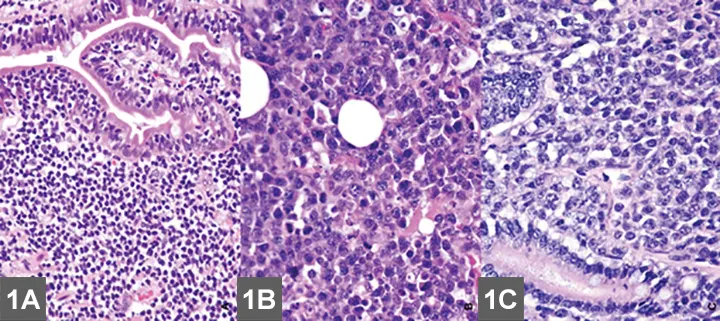

FIGURE 1

EATL type II (small cell) is the most common intestinal LSA in cats (A) and requires immunohistochemical labeling for proper phenotypic characterization and often PARR testing to differentiate from IBD. (B) EATL type I (large cell) occurs less commonly in the small intestine of cats, and neoplastic cells are often large granular lymphocytes. (C) Diffuse large B-cell lymphomas (DLBCL) occur most commonly in the stomach of cats or may present as part of multicentric disease. Although LSA diagnosis is usually made with routine microscopic examination, immunohistochemistry is required to accurately differentiate EATL type I from DLBCL (magnification 40×). Image and description courtesy of Matti Kiupel, Dr. vet. med. Habil, MS, PhD, DACVP, Michigan State University.

• Enteropathy-associated T-cell LSA (EATL) type I (high-grade or large cell/lymphoblastic GI LSA)1,6-7

• Typically involves more intermediate to large cells that display transmural invasion and often form masses (Figure 1B).

• Intermediate to large B-cell LSAs, including diffuse large B-cell  lymphoma (DLBCL), also occur with slightly less frequency (Figure 1C).

• Large granular LSA (LGL)—an aggressive subtype of EATL type I—is comprised of either cytotoxic T-cells or NK cells and characterized by multiple masses within the GI tract and other organ systems.8

• EATL type II

• The more common presentation of GI LSA characterized by diffuse superficial (mucosal/lamina propria) infiltration of small T-lymphocytes that often display epitheliotropism (Figure 1A).1,5-7

• Referred to as low-grade, lymphocytic, small cell, or indolent GI LSA, and associated with a slowly progressive disease course.1,5-7

Histopathology

• EATL type I is typically a straightforward histologic diagnosis.1,5-7

• EATL type II can be more difficult to confirm; it must be histologically differentiated from IBD (Figure 6, see gallery).1,5-7

• Characteristics more suggestive of EATL II over IBD include the presence of lymphoid infiltration beyond the mucosal layer, the presence of epitheliotropism, and certain characteristics of neoplastic lymphocytes.1,5-7

• Distinction can still be difficult without more advanced histologic techniques (see Table); how the biopsy is obtained is controversial.1,5-7

Immunohistochemistry (IHC) & Clonality Assay (PARR)

• Additional testing is necessary if diagnosis is equivocal after histological assessment.

• IHC identifies the neoplastic lymphocytes as T-cell or B-cell by staining for cell surface markers and can help differentiate IBD from EATL type II (Figure 8, see gallery).1,5-7

• PARR analysis confirms clonality, the hallmark of malignancy.1,5-7

• A recent study evaluating IHC and PARR noted that even though histopathology is highly specific for diagnosing feline GI LSA, sensitivity was enhanced by the addition of IHC and further improved by PARR.1,5-7